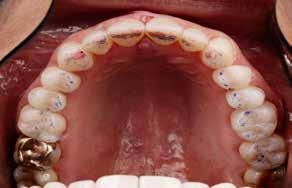

overbid (VOB). Papillen mellem 1+1 er betydeligt reduceret pga. fæstetab, og de mesialt kippede 1+1 har resulteret i en ”dark triangle”. Den facioorale funktion er for nuværende i.a. Panoramarøntgen (Fig. 1, I) viser marginalt knogletab i begge kæber og fravær af 8,7+7,8 og 8,7-8.

Objektivt anbefales behandling af det dybe bid, som ubehandlet forventes at forværres yderligere over tid. Patienten har ønske om behandling med æstetisk ortodontisk apparatur, alignere, og det vurderes muligt at behandle malokklusionen med alignere. Dog anbefales det generelt, at alignere undgås eller benyttes med væsentlige modifikationer af alignerens retention ved tandmobilitet, da dette ellers kan medføre jiggling, når aligneren tages af og på mange gange dagligt. På den anden side er der nogen evidens for, at alignerbehandling er associeret med bedre renhold og parodontal sundhed sammenlignet med fast apparatur (16).

Der planlægges alignerbehandling af begge kæber med intrusion af 1+1 og 2,1-1,2, nivellering af trangstilling UK med interproksimal reduktion (IPR) (Fig. 2 A, B) og senere IPR OK for reduktion af dark triangles mellem incisiverne efter nivellering. Patienten instrueres i at benytte alignere 20-22 timer/ dag med alignerskift hver 7. dag, og patienten ses hver 3.-8. uge under forløbet. Den første alignerserie består af 16 alignere for nivellering OK/UK og IPR i UK (Fig. 2). Efter denne serie planlægges IPR mellem incisiverne i OK for reduktion af dark triangles (Fig. 3) samt yderligere intrusion af OK og UK-fronten i 12 refinement-alignere. Patienten udviser god kooperation og er meget tilfreds med alignerapparaturet, som er mindre synligt end det faste apparatur (Fig. 4).